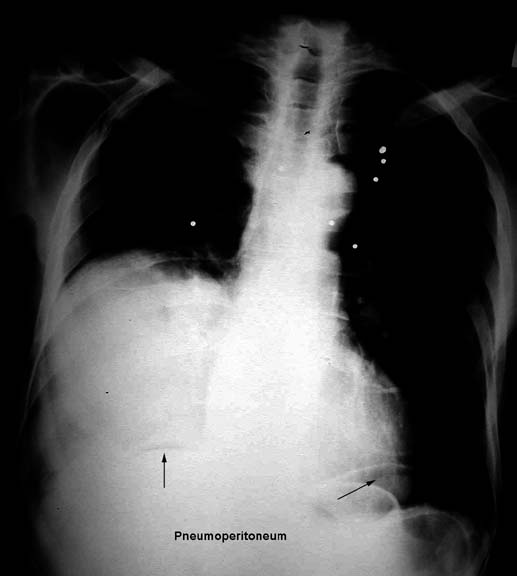

• Note pneumoperitoneum

• Pellets

Pellets